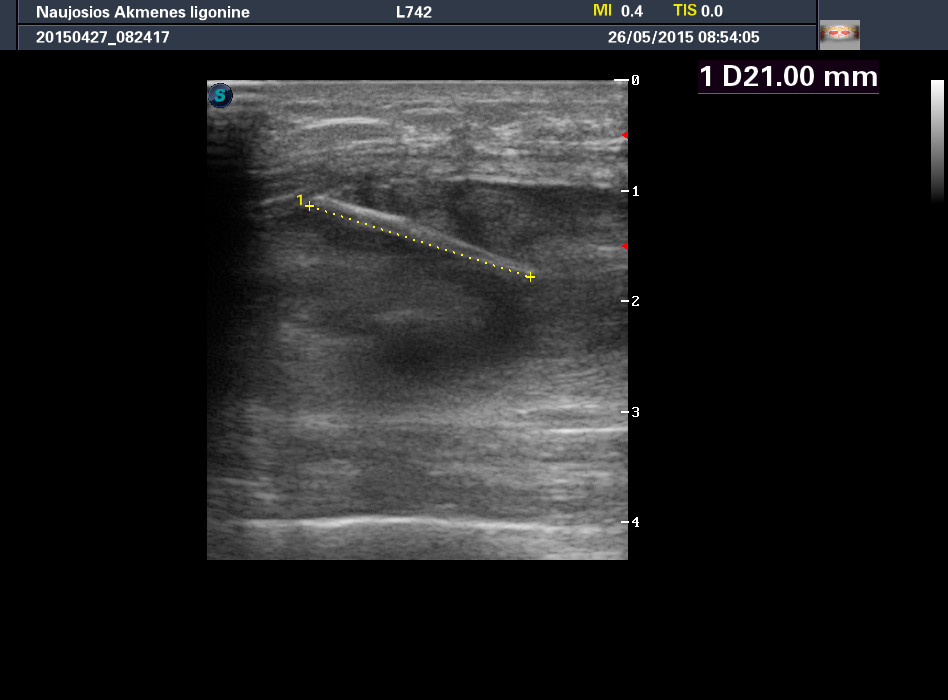

Молодой мужчина, деревенский житель, обратился к доктору по поводу образования на передней поверхности бедра, тот отправил на рентген (патологии не обнаружено), а затем УЗИ.

Травму пациент отрицает.

УЗИ мягких тканей бедра -- шип боярышника

Ультразвуковое исследование здесь было более информативным, чем обычный рентген, хотя если присмотреться, то и на рентгеновском снимке шип можно увидеть.